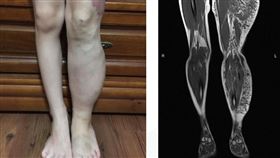

出生罹罕見血管腫瘤 她左腳比右腳大N倍

11歲的小柔出生時左腿有紅色斑點及血管瘤,且左下肢從...

2024/12/22 11:05